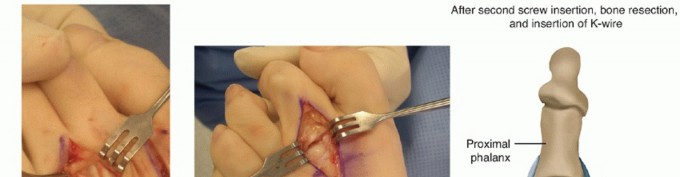

- TECH FIG 5 • A. A hand awl is used to make multiple perforations in the medial cortex of the proximal phalanx. B. K-wire stabilization after osteotomy completion and positional correction.

Davis et al3 described using a small awl to make multiple perforations at the base of the proximal phalanx opposite the direction of toe deviation (TECH FIG 5A).

After penetrating the appropriate cortex multiple times, taking care not to perforate the opposite cortex, finger pressure alone is used to complete the osteotomy and correct the underlying deformity (TECH FIG 5B).

A 0.045-inch K-wire is placed percutaneously if added stability is needed. -